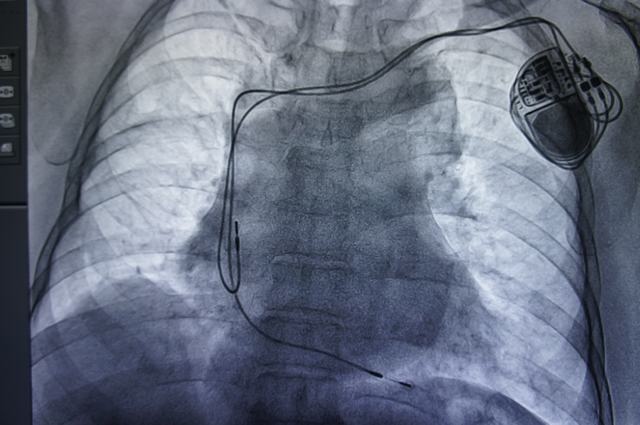

本网讯(黄鹤飞/文)近日,我院心内科为一例三度房室传导阻滞患者成功植入了全球首款经设计、测试和批准后可以在核磁共振成像(MRI)系统中安全使用的Advisa DR MRI SureScan 起搏器和导线系统。此后该患者不仅能行各项CT检查,同时也可以放心行各项核磁共振检查。据悉,这在我县及周边县市尚属首例。

这款美国美敦力公司研制的新型起搏器中增加了全新的MRI SureScan功能。在MRI扫描前开启该功能,暂时修改起搏器的数据收集和监控程序,同时提供必要的起搏功能。这一技术经过严格的测试和试验,目前是唯一通过美国食品药品监督管理局(FDA)认证可以在一定条件下安全进行MRI检查的起搏器和导线系统。同时,此款新型起搏器还保留了Advisa起搏器的所有诊断和治疗功能,包括诸如心衰预警、最小化右室起搏、室速监测、房颤干预等有益于术后患者管理的先进功能。